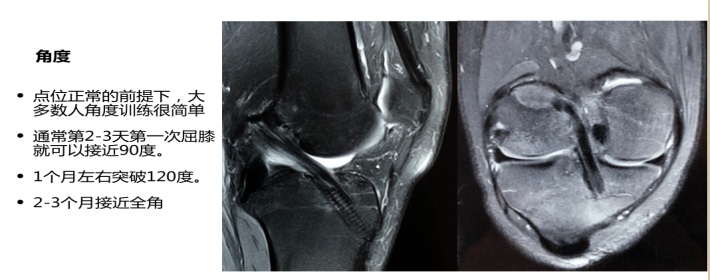

主讲人黄涛2012年毕业于运动人体科学专业,后进入北医三院运动医学科担任康复治疗师,2018年以来先后创建“骨间康复”、“北京葆石康复运动医学诊所”、“Bonespace Smart360足球直播比分 ”三家机构,“北京葆石康复运动医学诊所”目前已经发展为北京地区颇有影响力的运动康复机构。黄涛以《前交叉韧带损伤的治疗与康复》为题,结合了大量的临床资料和个人实践经验,用两个小时的时间介绍了前交叉韧带损伤的原因、症状、诊断(查体/影像)、手术、术后康复要点和方案等内容。讲座中展示了他参加临床手术或康复实践中采集的图片和视频材料,如大家熟知的检查前交叉韧带断裂的“抽屉试验”,以及“骨道”建立和韧带重建手术,把书本上刻板、枯燥、晦涩的知识,生动直观的展现在学生眼前。他用幽默的语言和丰富的案例积极与学生交流互动,并以自己在校学习和工作经历激励大家主动加强学习,在打好专业基础、拓展医疗知识、勤于动手等方面提升自身能力。